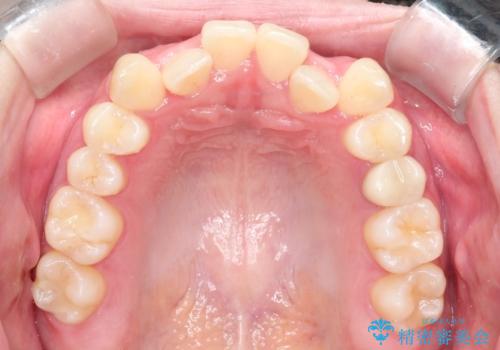

- 前歯のガタツキが気になるとのことで来院されました。

ワイヤー矯正とインビザライン矯正を併用することによって、治療期間の短縮と、より良い仕上がりを目指す治療を選択することとしました。

インビザライン(アライナー)矯正とワイヤー矯正のそれぞれの利点を生かした治療を行い、綺麗な歯並びになりました。